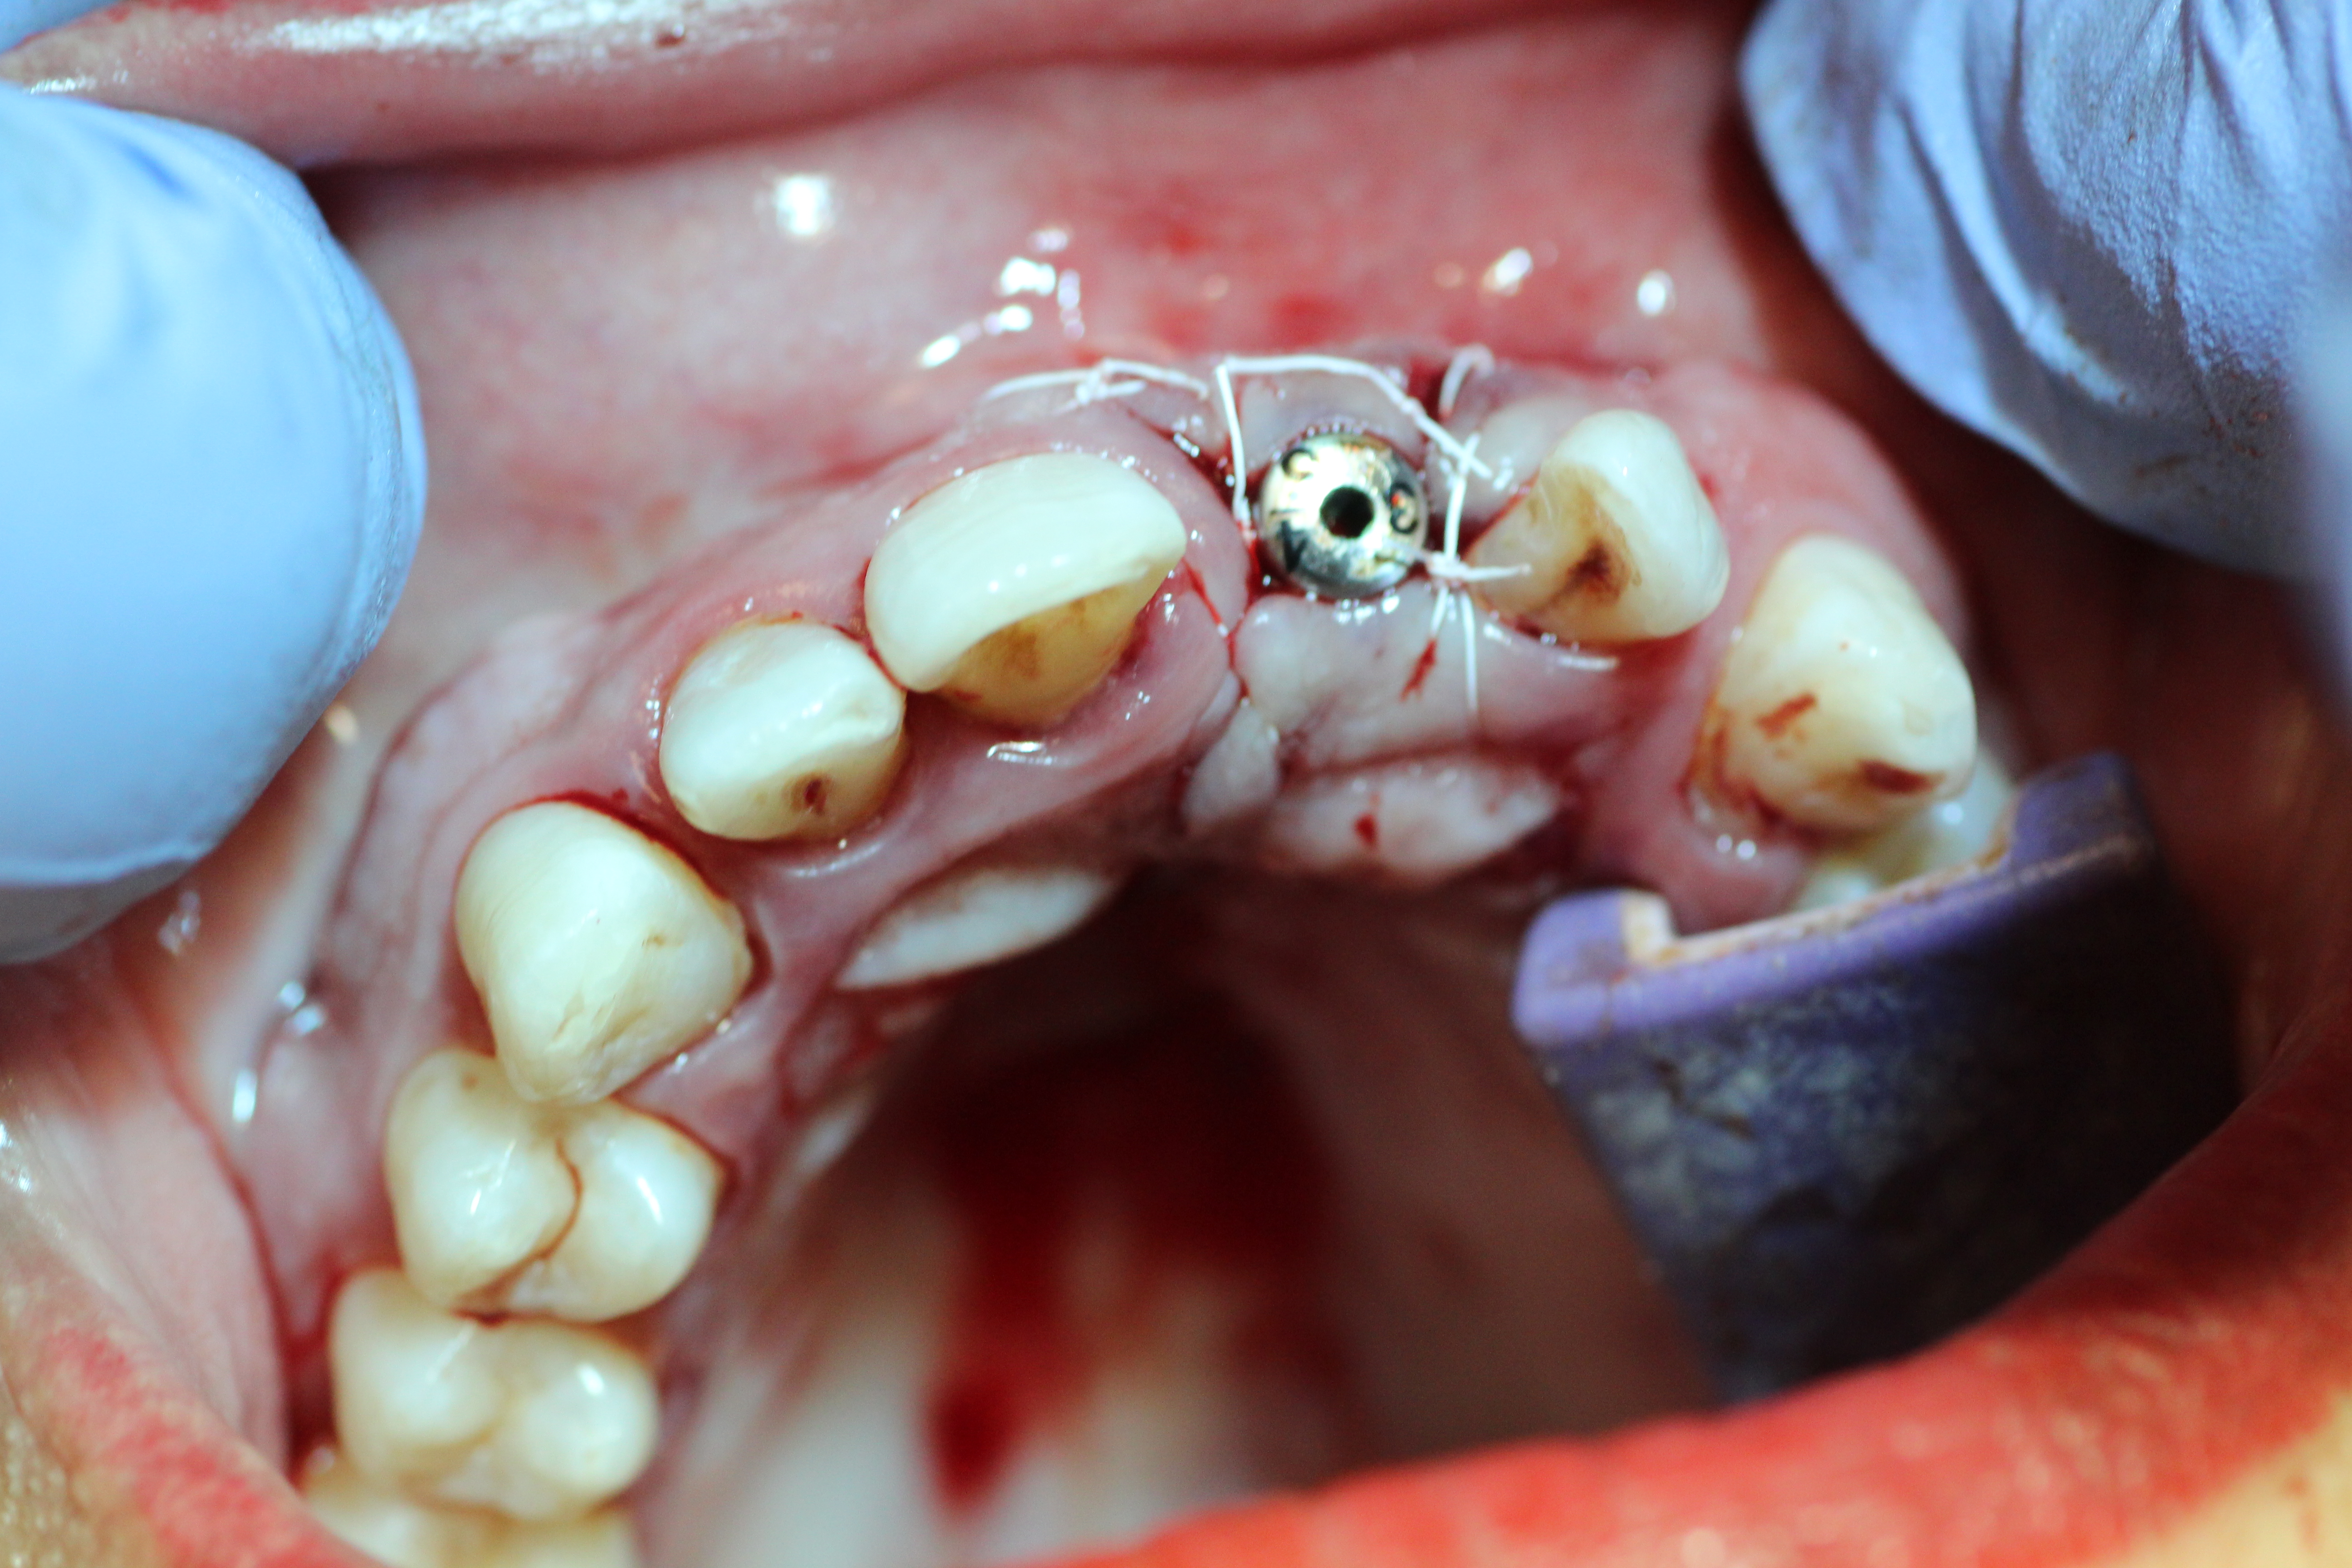

- Implant being placed.

-

- Implant being sutured while the temporary crown is being made.